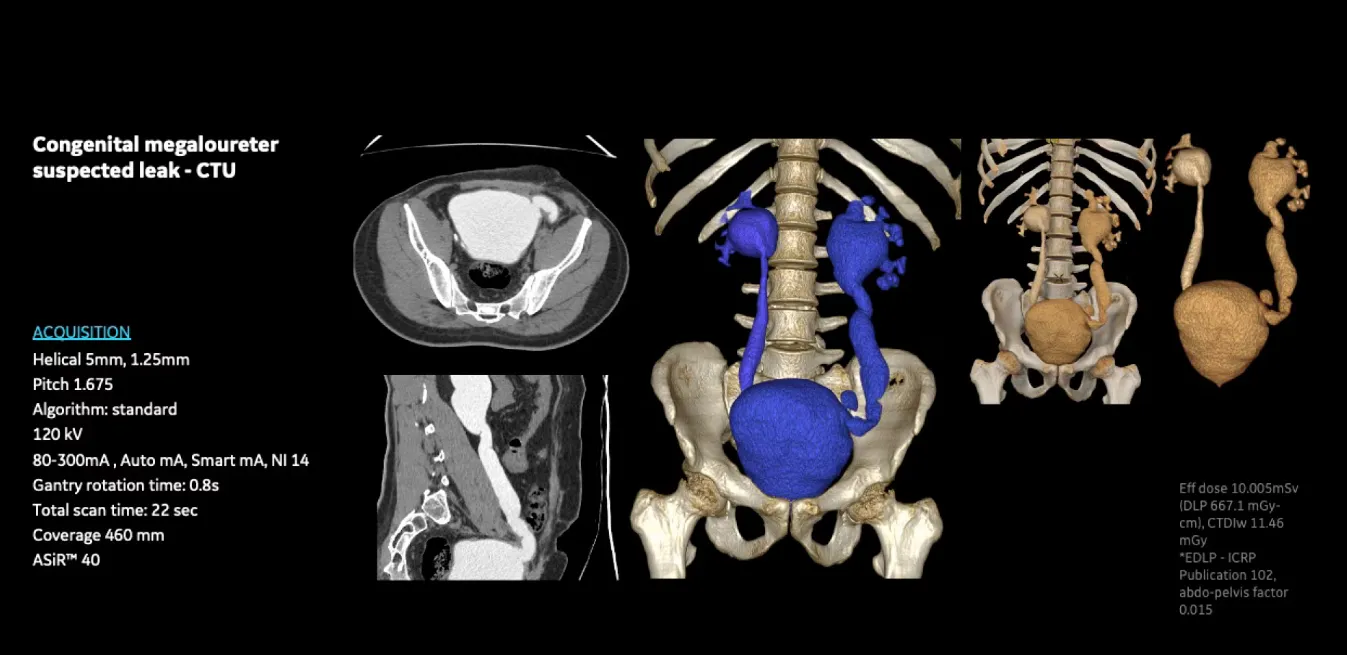

Клинические изображения

Revolution Aspire — это современный компьютерный томограф от GE HealthCare, разработанный как доступное и эффективное решение для рутинной КТ-диагностики. Он позволяет проводить высококачественные обследования большему числу пациентов при оптимальных затратах, сочетая скорость, точность и сниженную лучевую нагрузку.

• Высокая пропускная способность — скорость вращения гентри 0,8 секунды и оптимизированный рабочий процесс позволяют значительно увеличить количество исследований в день.

• Отличное качество изображений — инновационная цепочка визуализации Clarity (включая панельный детектор) обеспечивает высокое пространственное разрешение, низкий уровень шума и минимум артефактов.

• Снижение дозы облучения — технология ASiR (адаптивная статистическая итеративная реконструкция, опционально) позволяет уменьшить лучевую нагрузку до 40 % без потери диагностической ценности. Дополнительно используются модуляция дозы по органам (ODM), Dose Check и комплекс Smart Dose.

• Комфорт для пациентов — апертура гентри 70 см, стол с нагрузкой до 180 кг, сокращение времени задержки дыхания и быстрое сканирование делают процедуру удобной для пациентов разного возраста и телосложения (включая детей и полных пациентов).

• Надёжность и энергоэффективность — рентгеновская трубка 3,5 MHU с эффективным теплоотводом, генератор 42 кВт, проверенная конструкция обеспечивают стабильную работу при высокой нагрузке и сниженное энергопотребление.